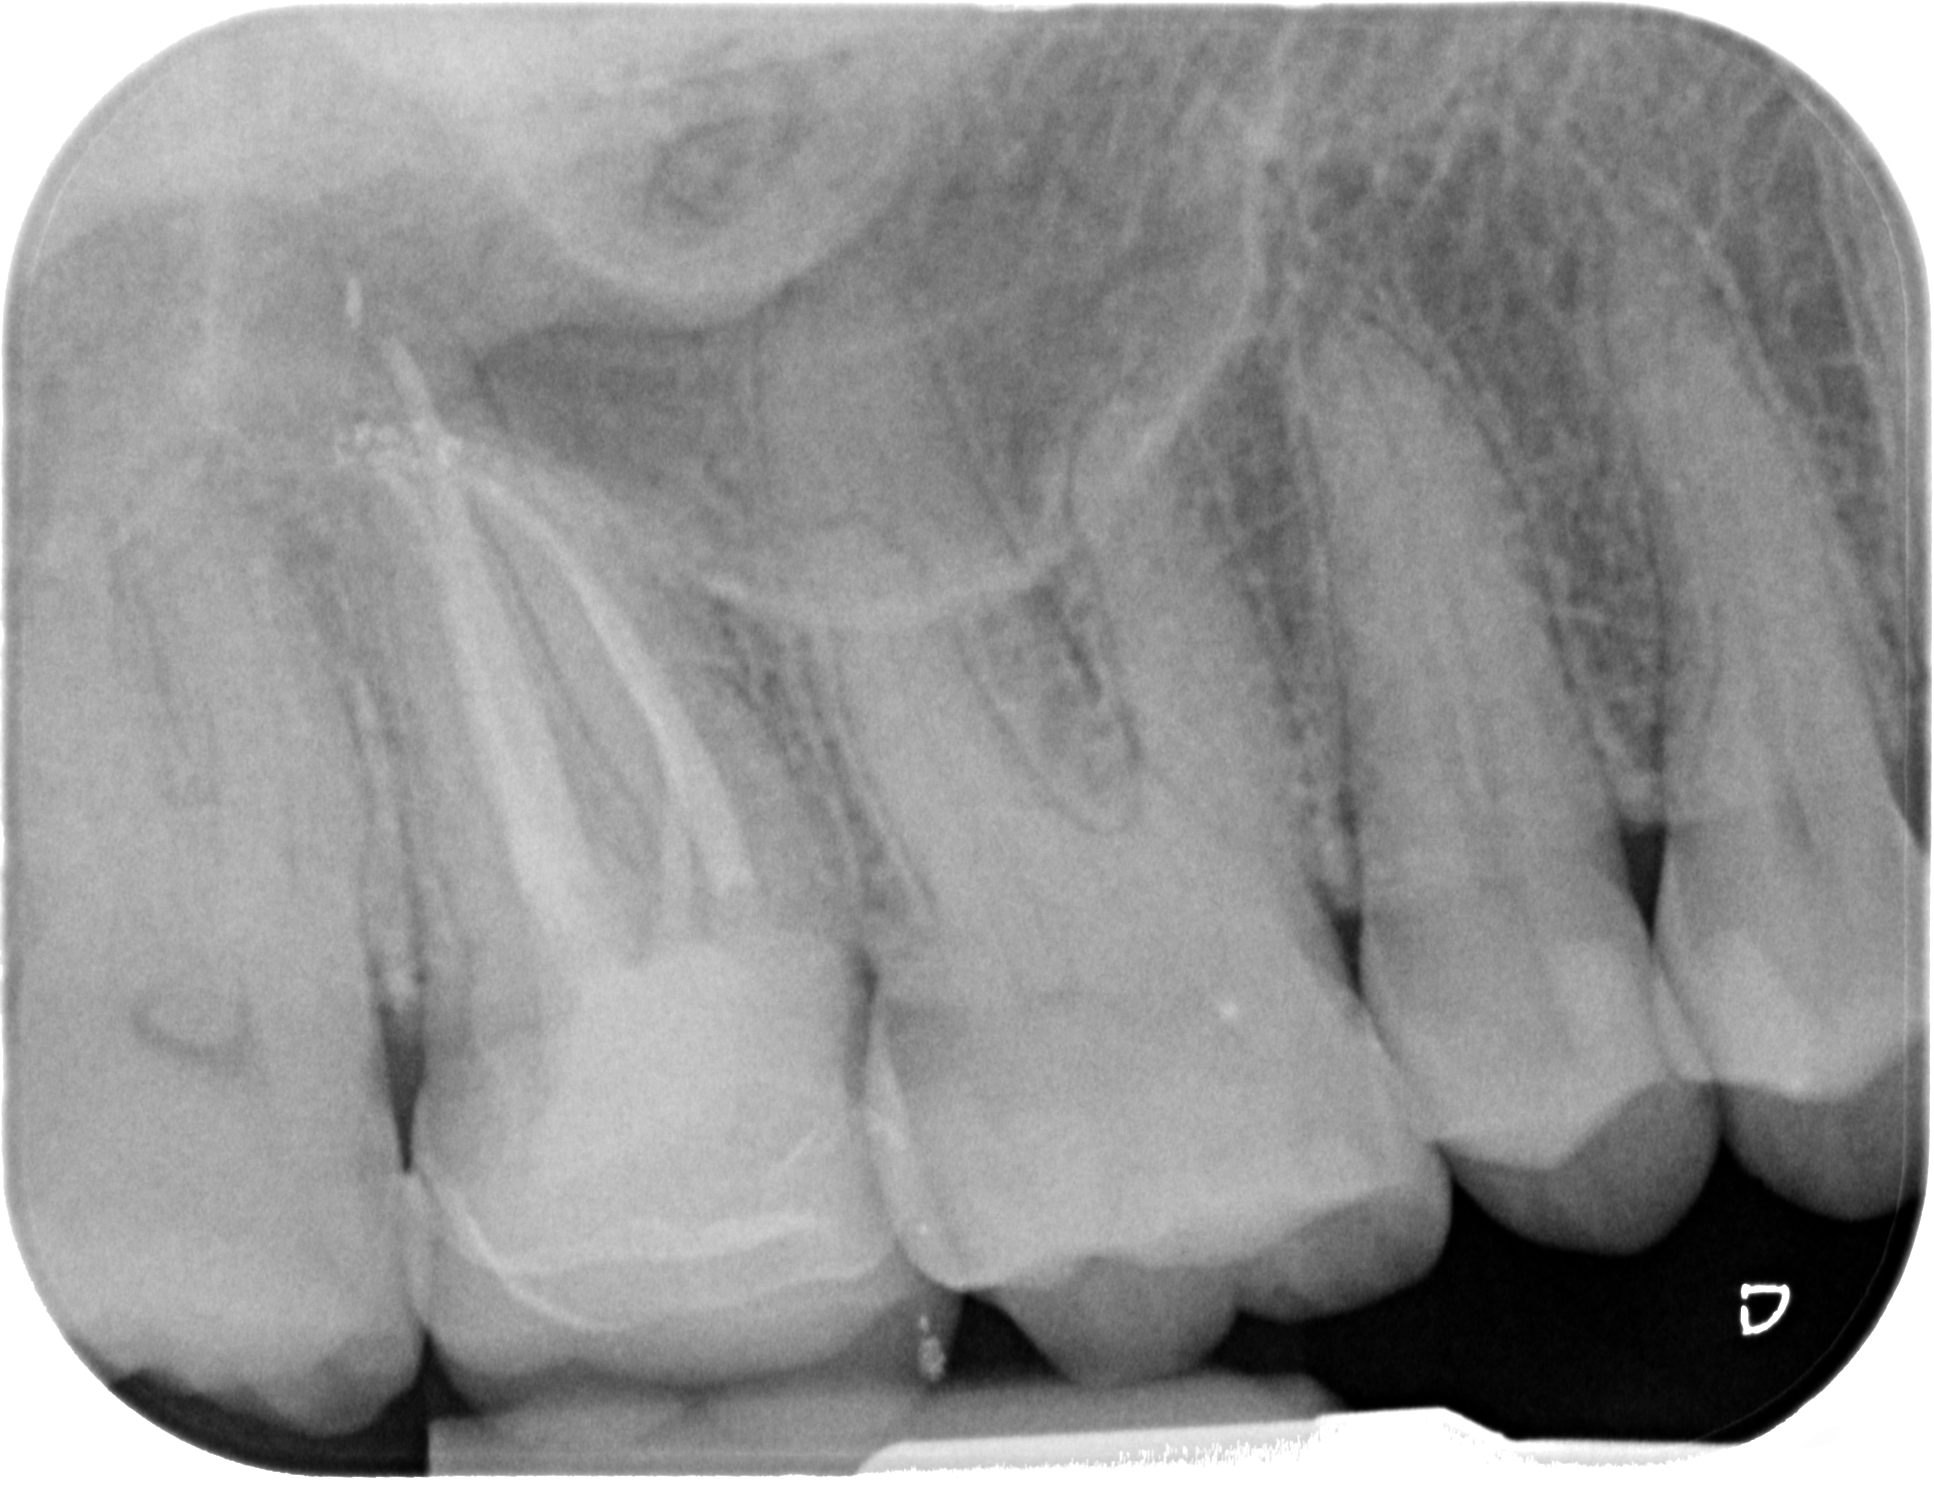

Lo step successivo, ossia l’esplorazione manuale e meccanica del sistema canalare, potrebbe nei casi più complessi essere impedito a causa dell’ostruzione dell’orifizio. Una calcificazione che si estende più in profondità rispetto al pavimento della camera pulpare può infatti rendere impossibile il sondaggio anche con lo strumento più piccolo a disposizione.

L’ostruzione, se estremamente limitata, può essere bypassata con un file montato su manico (micro-opener 10.04 15.04, Dentsply): questo strumento permette ottima visibilità e sensibilità rispetto ad un classico file manuale (Figure 21-26).

Questa azione di consumo selettivo della dentina può rendere visualizzabile in tempi molto brevi la traccia “bianca” di polvere depositata sull’orifizio; qualora invece i primi passaggi non avessero reso possibile la localizzazione è opportuno alternare irrigazione con ipoclorito di sodio e asciugatura per poi ripartire con un nuovo ciclo di escavazione (Figure 27-33).

Una volta localizzata la traccia del canale è necessario cercare di sondarlo anche per pochi millimetri con un micro opener o un K file di piccole dimensioni 06 o 08.

In questa fase di esplorazione va riposta molta attenzione nell’evitare di ostruirsi di nuovo la strada in direzione apicale: questo è possibile grazie a ripetuti lavaggi e alternanza di tentativi di sondaggio manuale senza forzare e affrettare la discesa fino a lunghezza di lavoro. A differenza degli inserti ultrasonici che tendono a creare un invito spesso appuntito in direzione apicale e ad annullare almeno parzialmente le tracce cromatiche, l’utilizzo di strumenti rotanti strategici come Endotracer preserva questi fondamentali punti di riferimento e anzi facilita l’accumulo di detriti dentinali proprio dove c’è una naturale depressione, vale a dire il lume canalare.